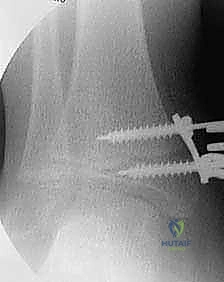

2. التصوير الشعاعي المتقدم:

لا يكتفي الدكتور هطيف بالفحص السريري، بل يتم إجراء صور أشعة سينية (X-rays) للقدم والكاحل أثناء وقوف الطفل (تحمل الوزن). يتم قياس زوايا دقيقة جداً لتقييم مدى الانحراف، مثل زاوية الساق والعقب (Tibiocalcaneal angle) وزوايا المفاصل الأخرى.

الخطوة الرابعة: تثبيت الشريحة (8-Plate)

بمهارة فائقة، يقوم الدكتور هطيف بوضع الشريحة المعدنية المصنوعة من التيتانيوم الطبي النقي فوق مركز النمو. يتم تثبيت الشريحة باستخدام مسمارين صغيرين؛ أحدهما فوق خط النمو والآخر تحته. هذه المسامير لا تخترق مركز النمو نفسه، مما يضمن عدم تدميره.